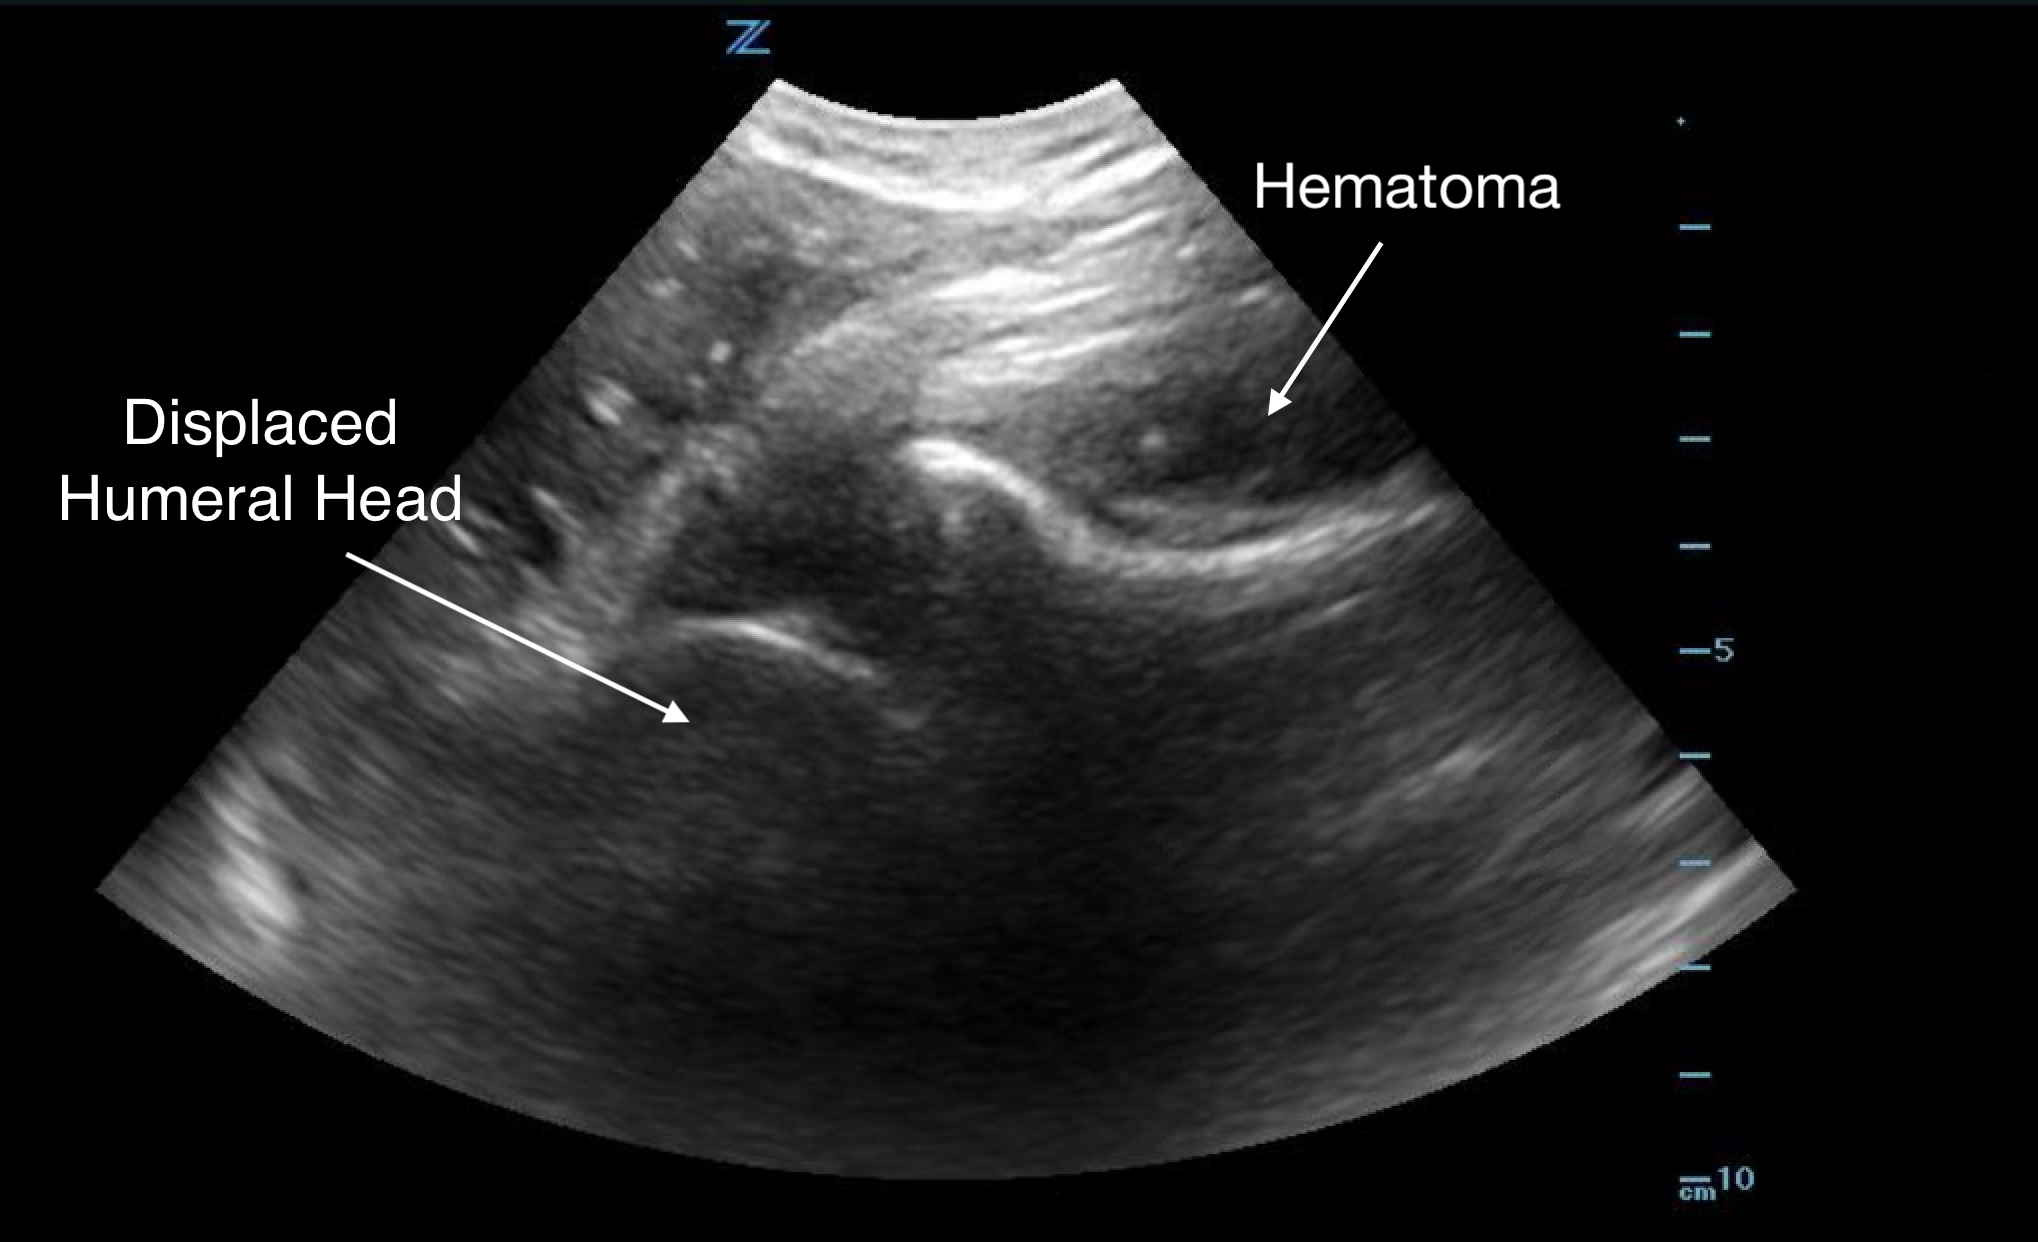

Shoulder Dislocation

Anterior Dislocation:

- The humeral head is displaced anterior to the glenoid.

- Appears at the bottom of the screen as the transducer is placed on the posterior shoulder.

- Movement is away from the transducer since the orientation is posterior-to-anterior.

Figure 9.

Anterior shoulder dislocation with overlying hematoma